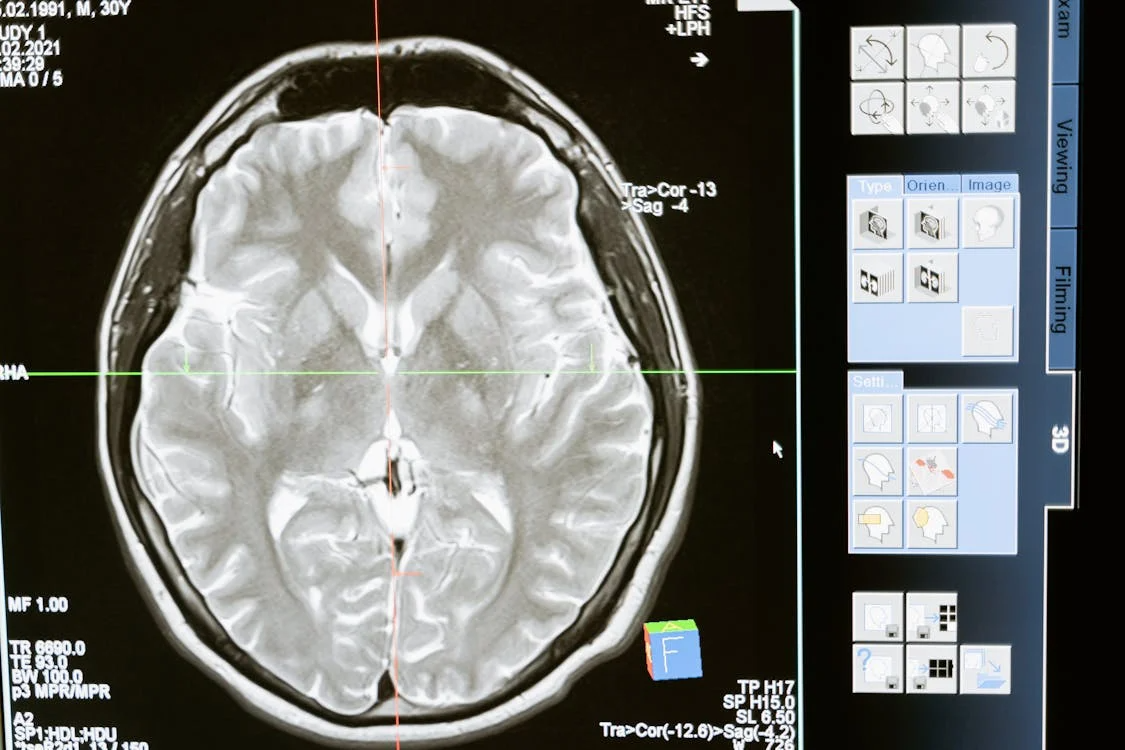

Researchers using brain scans have found that déjà vu activates the hippocampus and parahippocampal gyrus, regions linked to memory recognition. But unlike normal recall, déjà vu lacks the context that accompanies an actual memory. It’s your mind saying, “I’ve been here before,” without being able to tell when or how.

Interestingly, déjà vu has been observed in clinical settings among patients with temporal lobe epilepsy. In those cases, small bursts of electrical activity in the brain can induce déjà vu sensations before a seizure. This finding supports the theory that déjà vu is a neural hiccup—a false alarm from the part of the brain that checks whether something feels familiar.